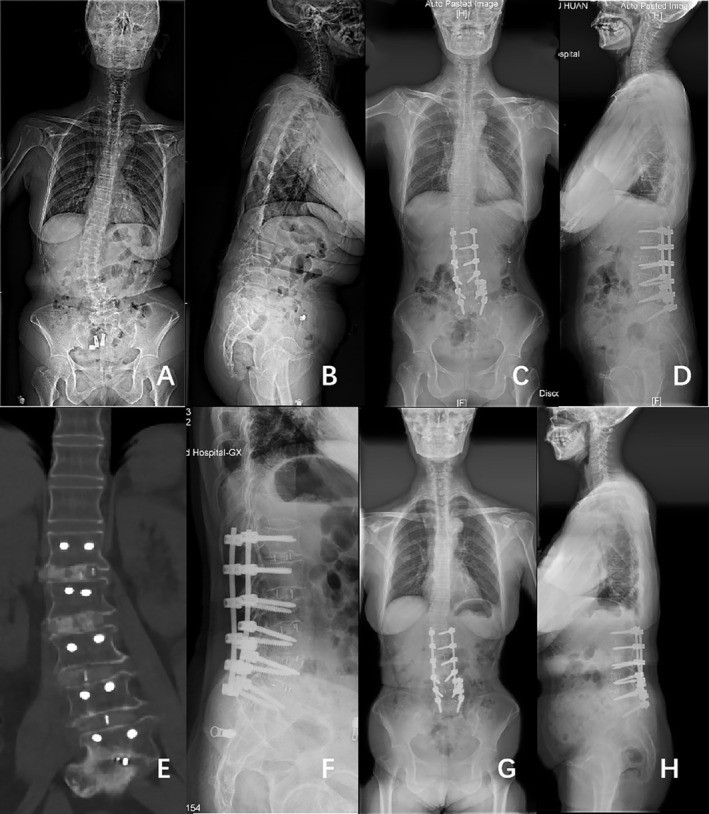

Figures 2 and 3 show classical examples of OLIF and posterior‐only approach surgery, respectively.